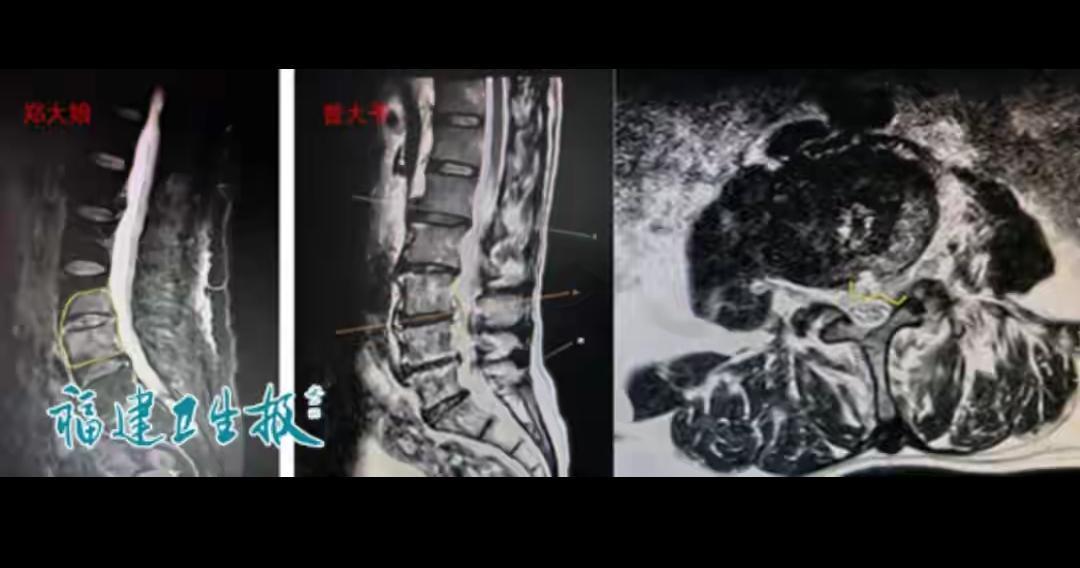

太可怕!别再把腰痛不当回事,不起眼的习惯,正在悄悄啃食你的骨头! 福建一对夫妻同时出现顽固腰痛,还伴随反复发烧,起初都以为是劳累和腰突,直到检查才发现,腰椎已被细菌严重侵蚀,险些造成瘫痪。元凶就是人畜共患的布鲁氏菌,多藏在牛羊身上,通过生奶、接触病畜侵入人体,专门攻击骨骼和腰椎。 很多人偏爱生鲜奶、觉得原生态更健康,却忽略了未消毒奶制品的巨大风险。这种病早期极易误诊,一拖再拖就会造成不可逆的损伤。比起盲目追求天然,守住饮食和接触的安全底线,才是对自己和家人最负责的做法。 健康从细节抓起,千万别让一时疏忽,换来难以挽回的后果。 你平时喝牛奶会特意选巴氏杀菌奶吗?